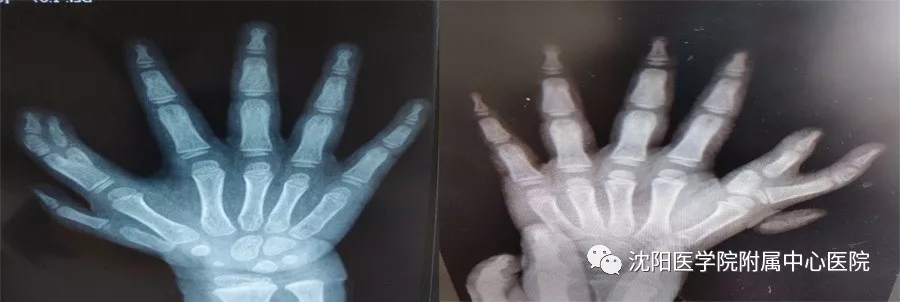

手术前

手术后